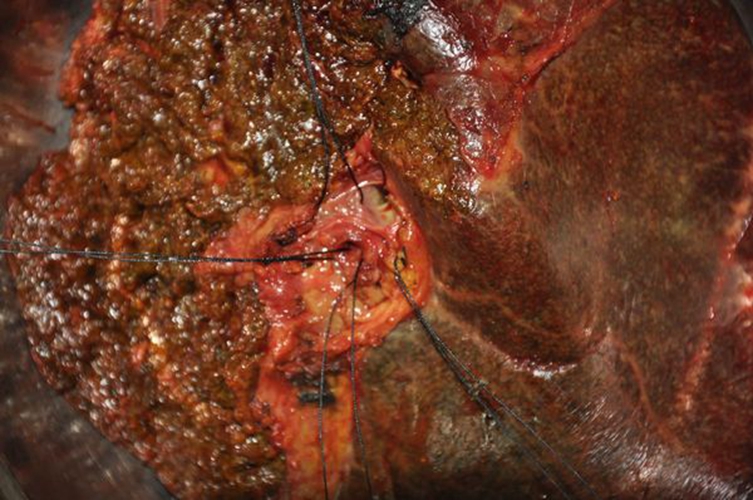

膽管癌圖片

高位膽管癌

肝門區膽管癌

肝門膽管癌晚期死後